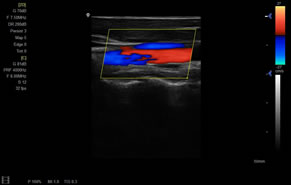

> 彩色血流量圖(CDE)

> 彩色血流分辨增強(qiáng)技術(shù)